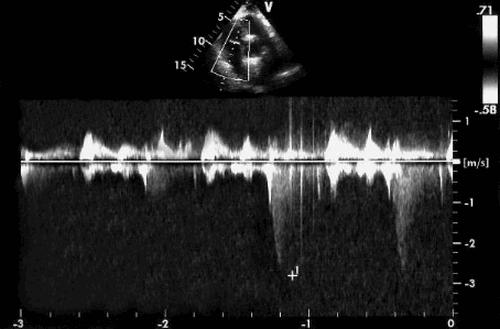

- Непрерывный волновой допплер на эхокардиографии: легкая митральная регургитация обычно прекращается намного позже (> 80 мс) конечного выброса, соответствующего снижению давления в левом желудочке во время изоволюмического периода. Короткая конечность замедления ретроградного трансмитрального сигнала предполагает значительную регургитацию. Когда давление в левом предсердии увеличивается, ретроградное падение давления на митральном клапане также падает и больше не представляет собой давление в левом желудочке. Давление в левом предсердии можно оценить как трансмитральное ретроградное падение давления, вычитаемое из систолического артериального давления, особенно когда оно низкое.